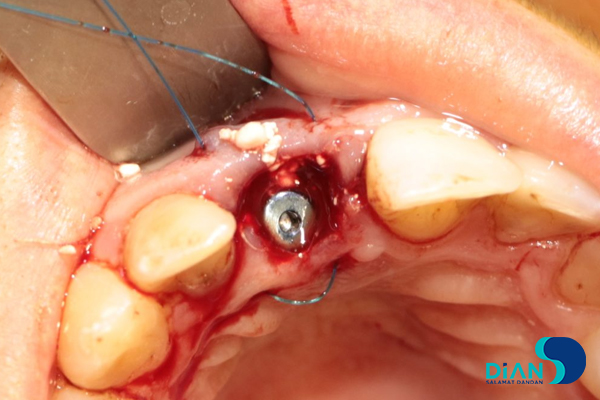

In the process of vestibular root fragment extraction the dentist found its interlocking with alveolar socket. There was a risk that a root fragment would break off with a part of alveolar socket. It was decided to apply «Socket shield» technique. The palatal root fragment was removed.

Then the dentist polished remained root part and conducted alveoli curettage.

The alveolar socket was washed with antiseptic solution, and then the dentist made osteotomy while considering the future correct position of dental implant in the socket in relation to 12, 21 and 31 teeth.

He formed implant bed by following Bio3surgical protocols.

Bio3 implant Progressive 3.8/13 was entered from the box and fixed with 20-25 N/cm2 loading.

Cover screw was placed.

The gap between the implant and the tooth root was filled with bone material.

The screw cap was replaced by the healing abutment.

The gum edges were sutured with U-shaped seam.